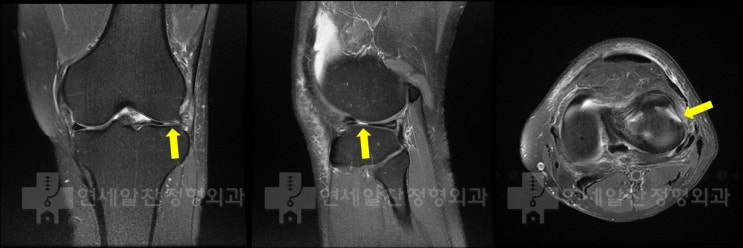

슬관절 통증의 진단에서 history taking, 이학적 검사의 중요성

50세 여자환자가 무릎 통증을 주소로 내원하였다. 환자는 2개월전 턱에 걸려 넘어지면서 무릎이 꺽이면서 ...